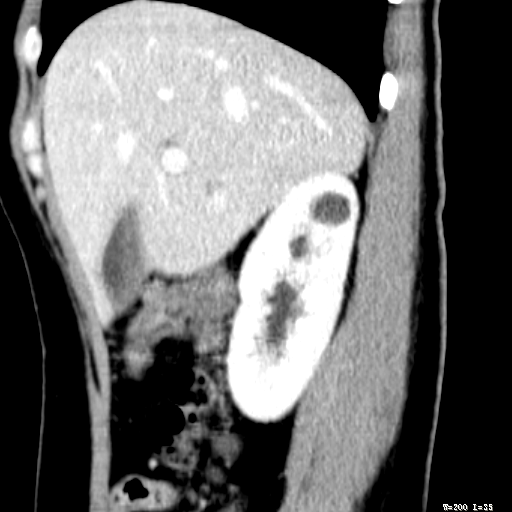

标题: CT25345:右肾占位。 [打印本页]

标题: CT25345:右肾占位。

女,30岁,右腰部胀痛3个月。

增强无明显强化,先考虑血管平滑肌脂肪瘤,建议作薄层扫描右mri检查,

增强无明显强化,先考虑血管平滑肌脂肪瘤,建议作薄层扫描右mri检查

考虑右肾近上极囊肿;建议必时行mri检查。